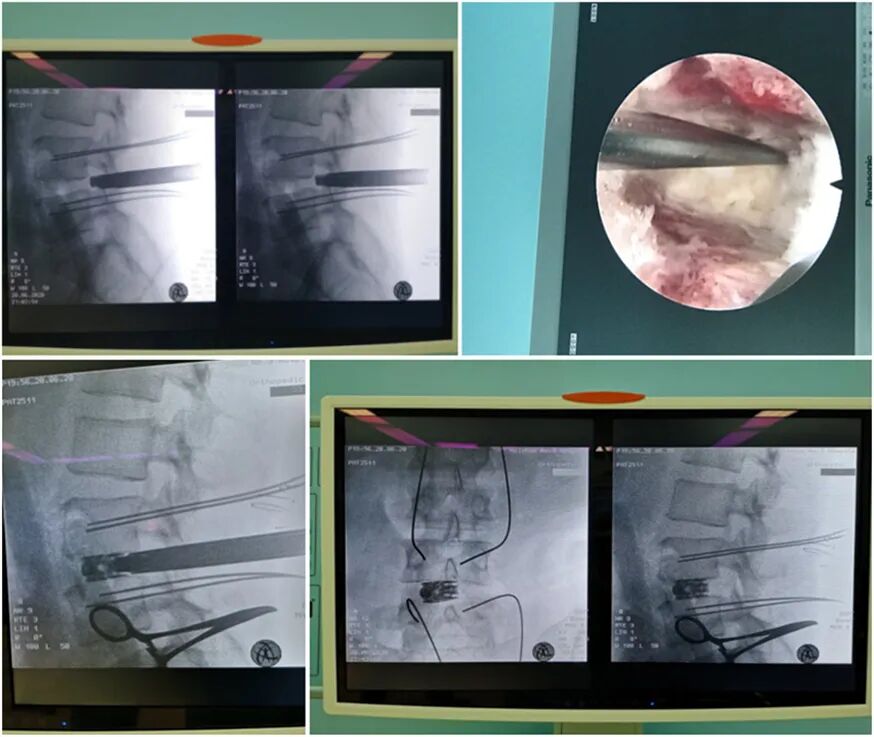

隨著脊柱微創(chuàng)技術(shù)的不斷發(fā)展,微創(chuàng)椎間融合術(shù)的概念早已深入人心,越來越多的腰椎退行性病變患者將微創(chuàng)手術(shù)作為首選。2020年6月20日,惠州三院骨科醫(yī)學(xué)中心脊柱外科完成了第一臺(tái)全內(nèi)鏡下腰椎微減壓椎間融合術(shù)(下稱PE-TLIF)。手術(shù)3個(gè)小時(shí)順利完成,現(xiàn)患者已康復(fù)出院。

術(shù)前定位

術(shù)中透視

PE-TLIF技術(shù)是一種微創(chuàng)椎間融合技術(shù),手術(shù)方案為經(jīng)椎間孔入路,使用上關(guān)節(jié)突導(dǎo)向切除裝置定向磨除上關(guān)節(jié)突,擴(kuò)大椎間孔區(qū)域,在直徑僅7毫米的脊柱內(nèi)窺鏡輔助下進(jìn)行腰椎的減壓、椎間植骨及融合器植入,最后輔以經(jīng)皮置入椎弓根螺釘。該技術(shù)通過較小的創(chuàng)傷,既能達(dá)到與開放腰椎減壓融合手術(shù)同樣的臨床效果,又能減少并發(fā)癥,實(shí)現(xiàn)病人快速康復(fù)的目的。